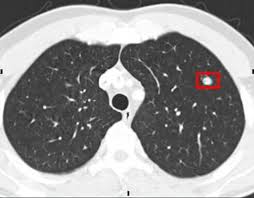

폐결절(pulmonary nodule)은 폐 안에 지름 3cm 이하의 작은 덩어리나 불투명 부위로, 흉부 X‑선이나 CT 검사에서 우연히 발견되는 경우가 많습니다. 대부분은 무증상이며, 양성인 경우가 많지만 일부는 악성(암)일 수 있어 주기적인 관찰이 필요합니다.

- 흉부 X‑선 또는 흉부 CT로 발견

- 결절 크기·형태·경계·석회화 여부 등 특징 분석